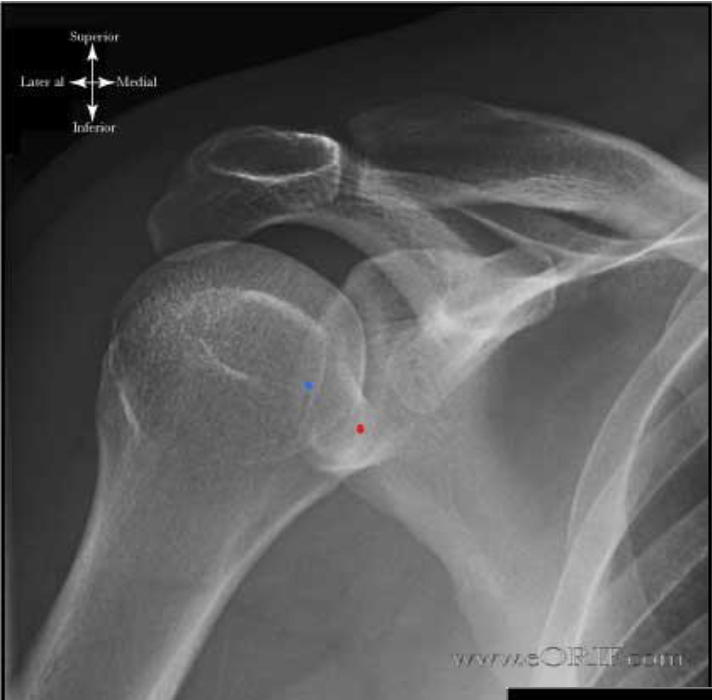

What is this view of the shoulder? what views are missing?

AP internal rotation

MISSING:

AP

AP external rotation

Axial

Scapular Y Shoulder

AC Joints (spot, weighted